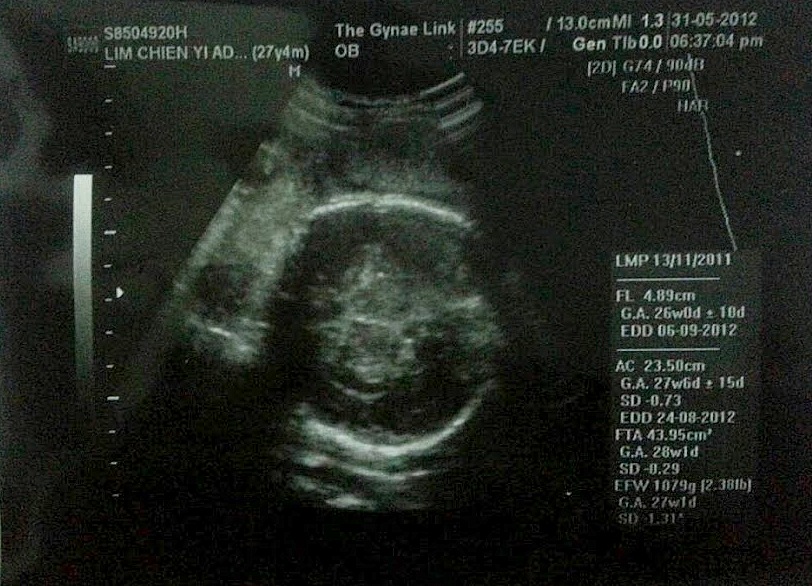

Had my routine checks ups on 31st May just couple of days back with Dr Don. Gained 2kg from my last check on 3rd May. Total I gained 12.2kg as for now. I'm 27 weeks pregnant for the second time.

my growing belly. My belly show more compared to the first time!